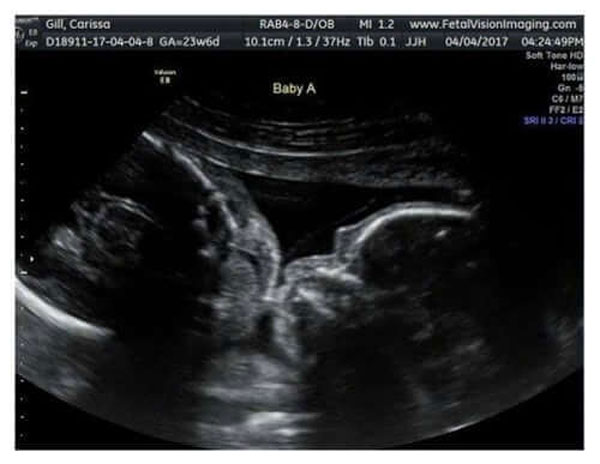

ಕ್ಯಾರಿಸ್ಸಾ ಗಿಲ್ ಎಂಬ ತಾಯಿ ಫೇಸ್ಬುಕ್ ಅಲ್ಲಿ ಹಂಚಿಕೊಂಡ ಈ ಫೋಟೋದಲ್ಲಿ ಆಕೆಯ ಹೊಟ್ಟೆಯೊಳಗಿರುವ ಅವಳಿ-ಜವಳಿ ಮಕ್ಕಳು ಒಬ್ಬರಿಗೊಬ್ಬರು ಮುತ್ತು ನೀಡುತ್ತಿರುವುದನ್ನ ಕಾಣಬಹುದು!